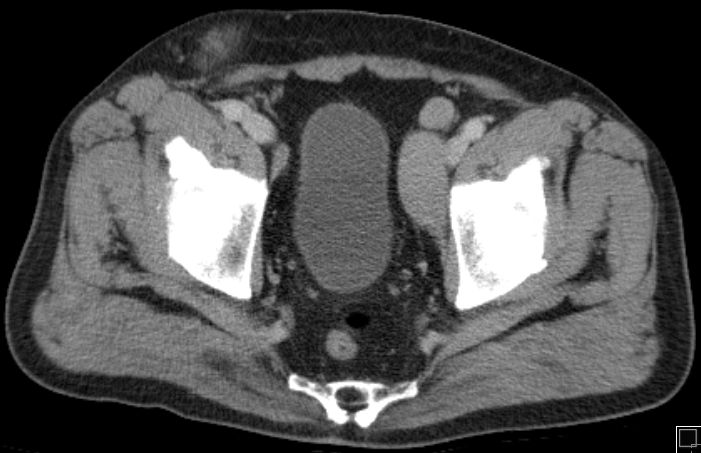

inguinaler Bulk |

72-jähriger Mann mit Verdacht auf

Hernia inguinalis rechts. PE: diffuses großzelliges B-Zellymphom.![]() |

Befall der Nl. iliaca externa![]() | ||